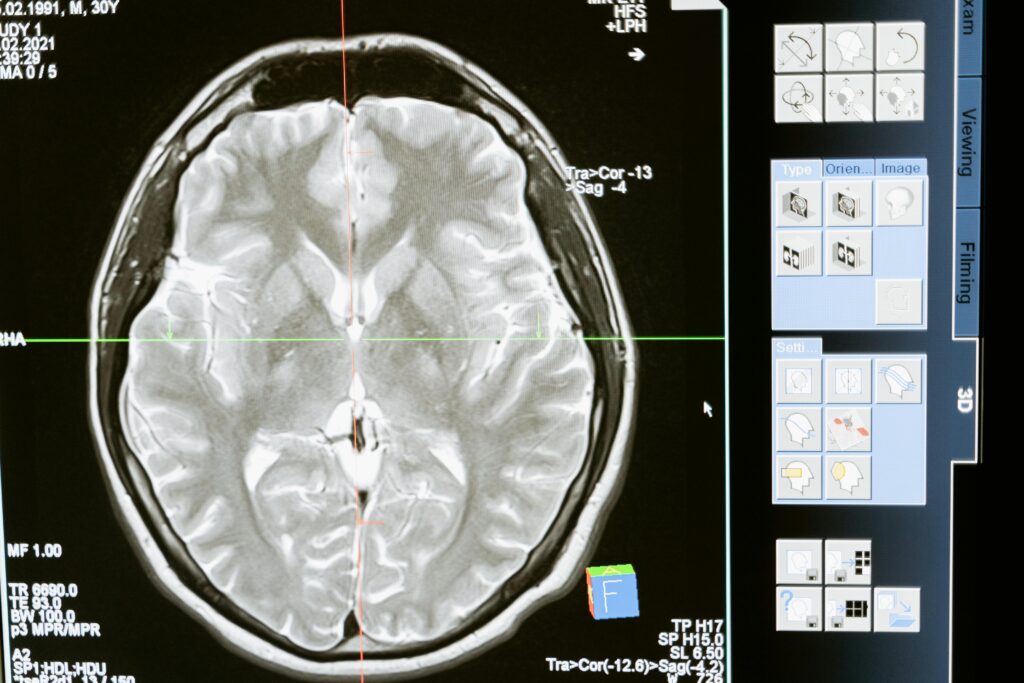

Best Neurologist in Tricity, Dr. Pradeep Sharma offers expert treatment for stroke, epilepsy, migraine, back pain & neurological disorders. Book appointment today.

Dr. Pradeep Sharma is a distinguished neurologist with extensive experience in diagnosing and managing complex neurological conditions. Known for his clinical excellence and compassionate care, he has built a strong reputation as one of the most trusted neurologists in the Tricity region. With a solid academic foundation including MBBS, MD (Medicine), and DM (Neurology), along with FIPM in Pain Management, Dr. Sharma combines deep medical knowledge with modern treatment approaches. He is dedicated to staying updated with the latest advancements in neurology, ensuring patients receive cutting-edge and effective treatments tailored to their needs.

We utilize advanced diagnostic technology to ensure accurate detection of neurological conditions, combined with personalized treatment plans tailored to each patient’s needs. With the expertise of Dr. Pradeep Sharma, patients receive experienced and reliable care, delivered with a compassionate approach focused on comfort, trust, and long-term recovery.